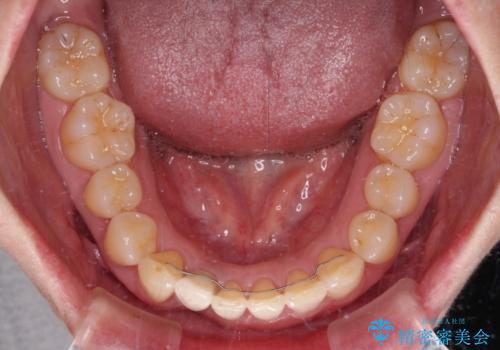

- 下顎前歯が抜けそうとのことで来院された患者様です。

初診の状態ではすぐにでも抜けそうな状態で、インプラントによる補綴治療を行うこととしました。

インプラント治療に際し、前歯の叢生に対する矯正治療を提案したところ、興味を持たれたので、インビザライン・ライトによる矯正治療を行うこととしました。

抜歯後にスペースができると恥ずかしいため、抜歯した歯を接着剤で固定した上で矯正治療を行い、その後インプラントやオールセラミッククラウンの装着を行うこととしました。